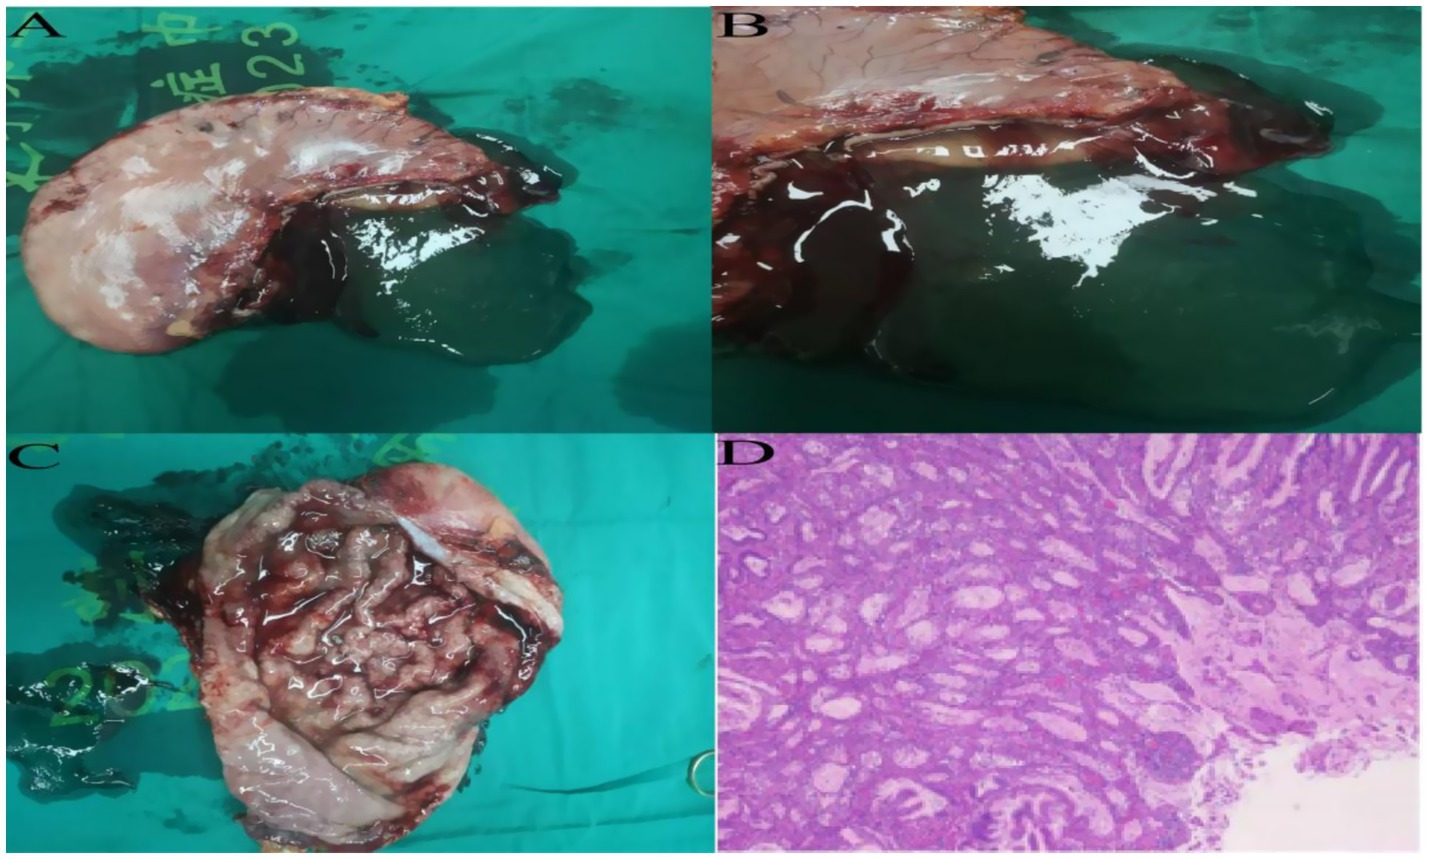

4. The abdominal cavity was irrigated with warm saline and hemostasis achieved. Two drains were placed—one behind the esophagojejunostomy and one in the left upper abdomen—exteriorized and secured through lateral abdominal wall trocar sites (Supplementary Video S1). Instrument and gauze counts were accurate. The abdomen and trocar sites were closed in layers. Gross specimen showed diffusely thickened gastric wall, coarse and disordered mucosal folds, and abundant yellow-white viscous secretions in the gastric lumen (Figures 3A–C). The procedure was uneventful, lasting 245 min with approximately 20 mL intraoperative blood loss.

Figure 3. (A–C) Postoperative total gastrectomy specimen reveals diffuse thickening of the gastric wall, with prominent and disorganized mucosal folds, and a significant accumulation of yellow-white viscous secretions within the gastric lumen. (D) Postoperative specimen routine pathology results, hematoxylin and eosin staining, high-power microscopy.

On postoperative day 3, the patient passed flatus and gradually resumed oral intake. Upper GI contrast on day 6 showed a patent anastomosis with smooth passage (Figure 4A). Sutures and the left upper abdominal drain were removed at 1 week. On day 12, abdominal CT confirmed anastomotic patency with no significant abnormalities (Figure 4B). The posterior esophagojejunostomy drain was removed, and the patient was discharged. Supportive care included albumin supplementation, nutritional support, regular dressing changes, and monitoring of liver and renal function. The patient recovered well, tolerated diet, albumin normalized, and no complications occurred. Pathology revealed marked mucosal fold hypertrophy, severe chronic active inflammation with erosion, congestion, edema, prominent foveolar hyperplasia with mucinous change, distortion, and dilation, foveolar extension to the muscularis mucosae, and reduced acid glands, consistent with Menetrier’s disease (Figure 3D). Immunohistochemistry: CEA (partial+), CK (broad-spectrum+), Ki67 (normal proliferative pattern), MUC-2(−), MUC-5 AC (foveolar+), MUC-6 (focal+), P53 (wild-type).

7. Postoperative specimens showed diffuse gastric wall thickening, coarse and disorganized mucosal folds, and abundant yellow-white viscous secretions. Literature suggests that imbalance between mucus and acid secretion leads to protein malabsorption and subsequent hypoproteinemia (16).